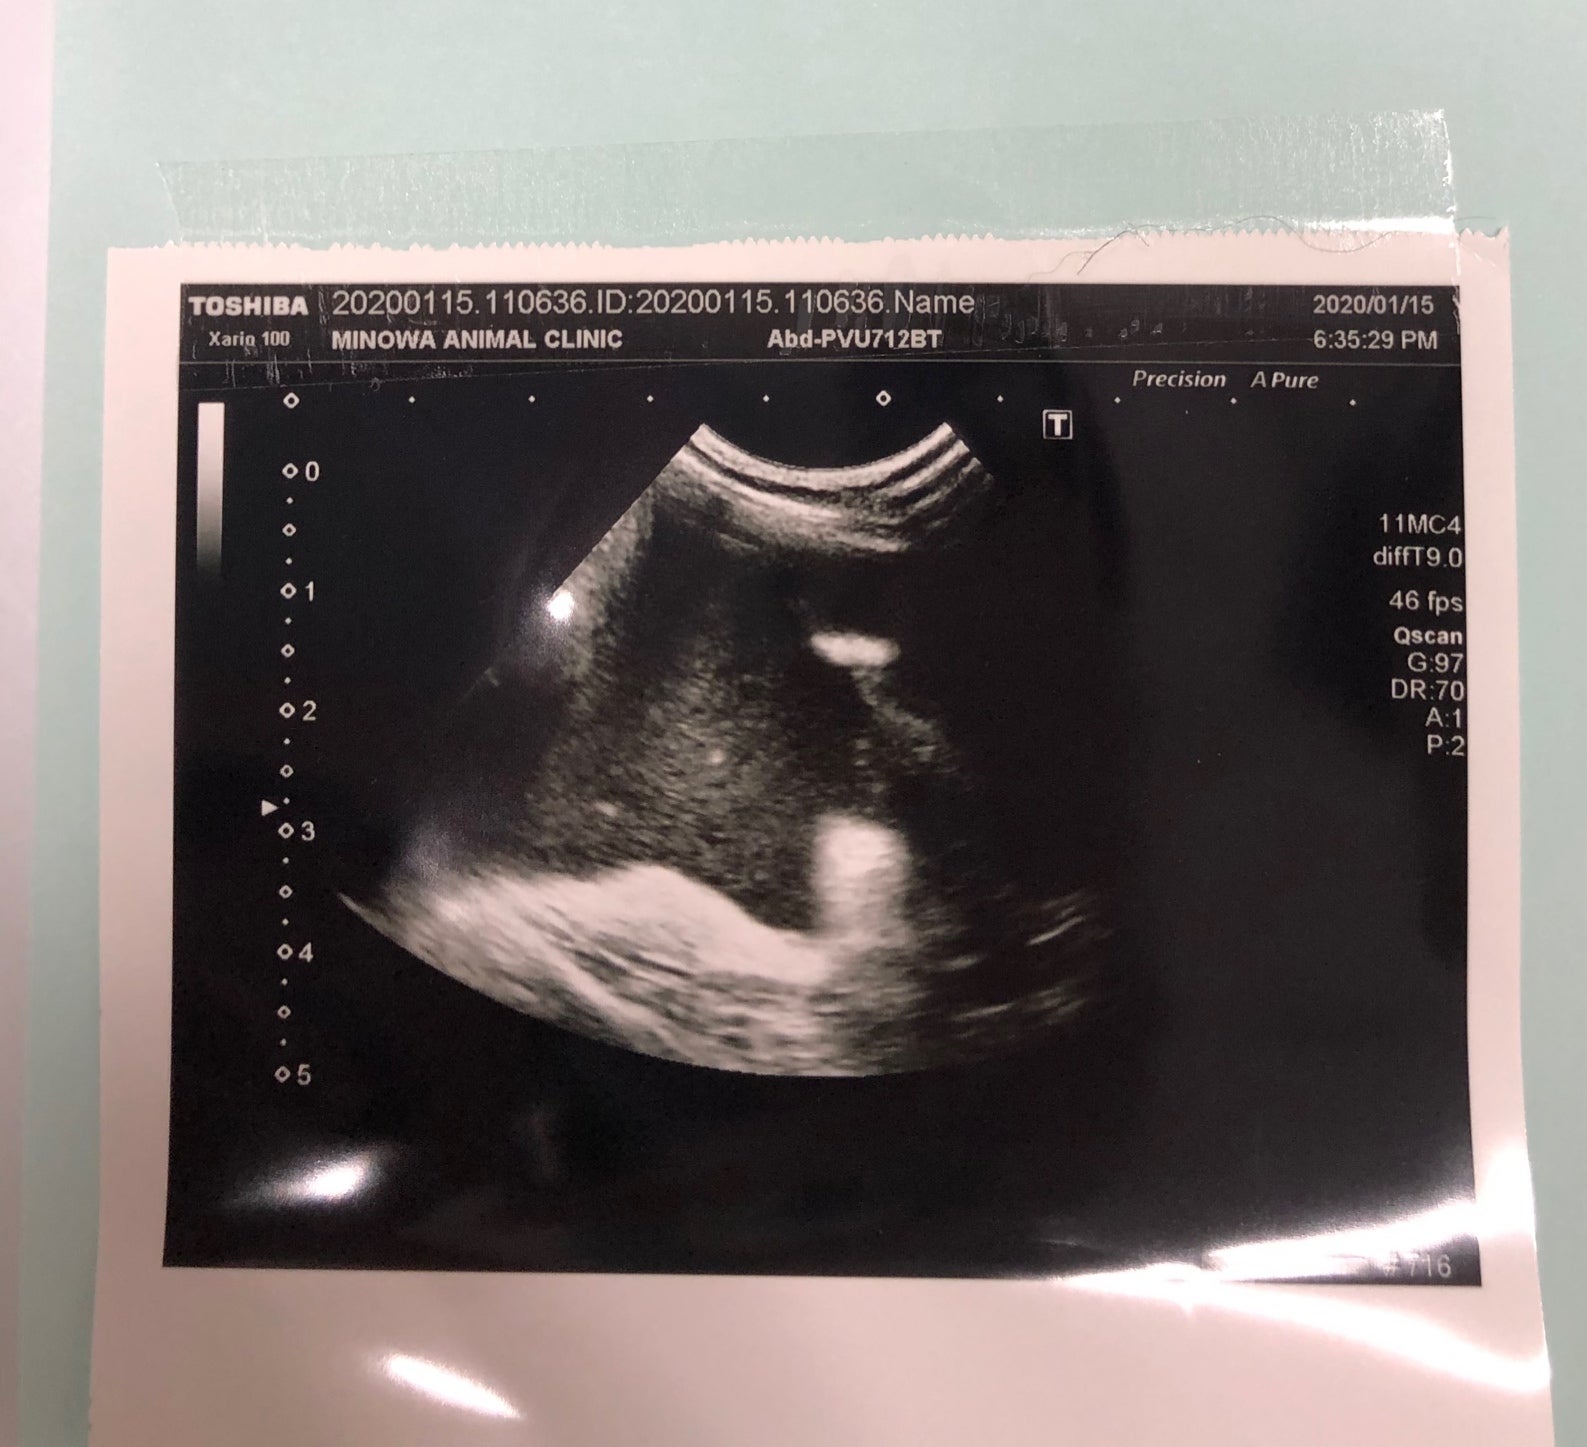

マロはウエットタイプで、初回診療時既に少量の腹水が溜まっていることが確認されました。

(こちらは腹水中のウイルス検査結果です)

その後、40度を超える高熱と血液検査から白血球数が異常に増えており体内で炎症を起こしていると説明を受けました。